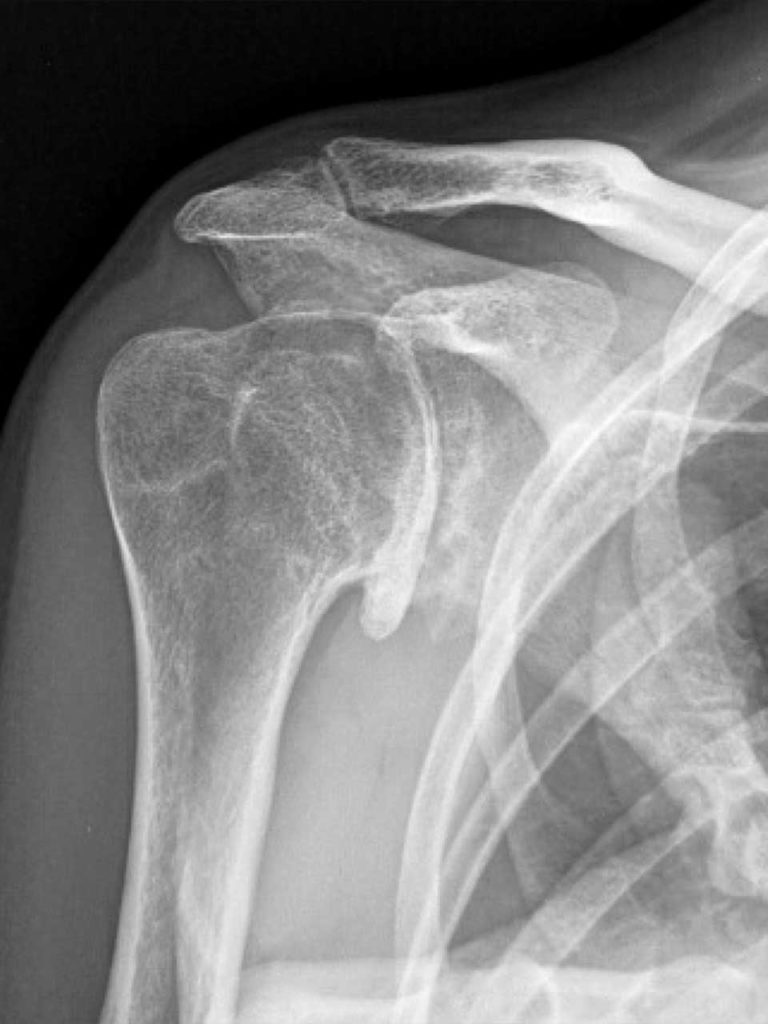

Voici la radiographie préopératoire. Image fournie par le Dr. Stephanie Muh.